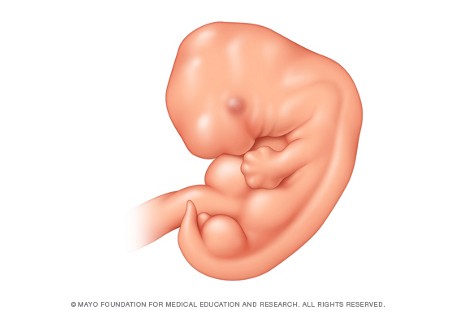

6. Minggu ke-7: Kepala Janin Berkembang

Foto: Mayo Clinic